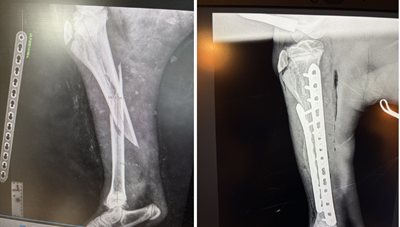

The baby alpaca was then brought into Cliffe’s dedicated equine hospital for an X-ray, where the clinical team confirmed he had suffered a tibial fracture. Due to the location of the break, Major required surgery rather than treatment with a cast alone.

“We performed the procedure in the equine hospital’s theatre, where he had two locking plates applied in order to stabilise the fracture,” explained Mark.